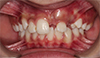

Central Lying Over the Lateral

Do you think this is an extraction case in the upper? Can the lateral be safely moved distally, clearing the path for the central?